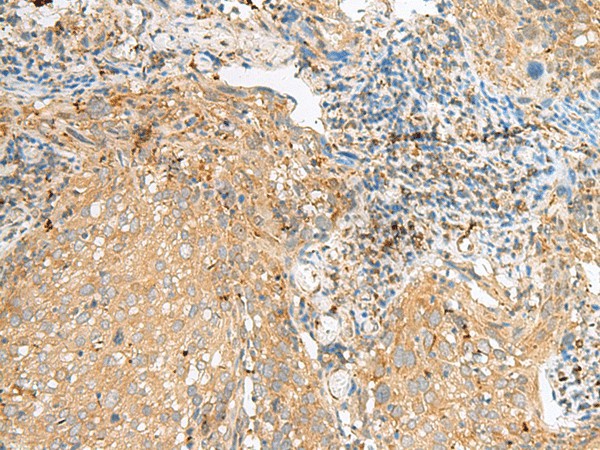

COPE Polyclonal Antibody (E-AB-52730)

| Валидировано для | IHC WB Иммуногистохимия; Вестерн-блоттинг |

| Рекомендуемые разведения | WB 1:500-1:2000; IHC 1:50-1:300 |